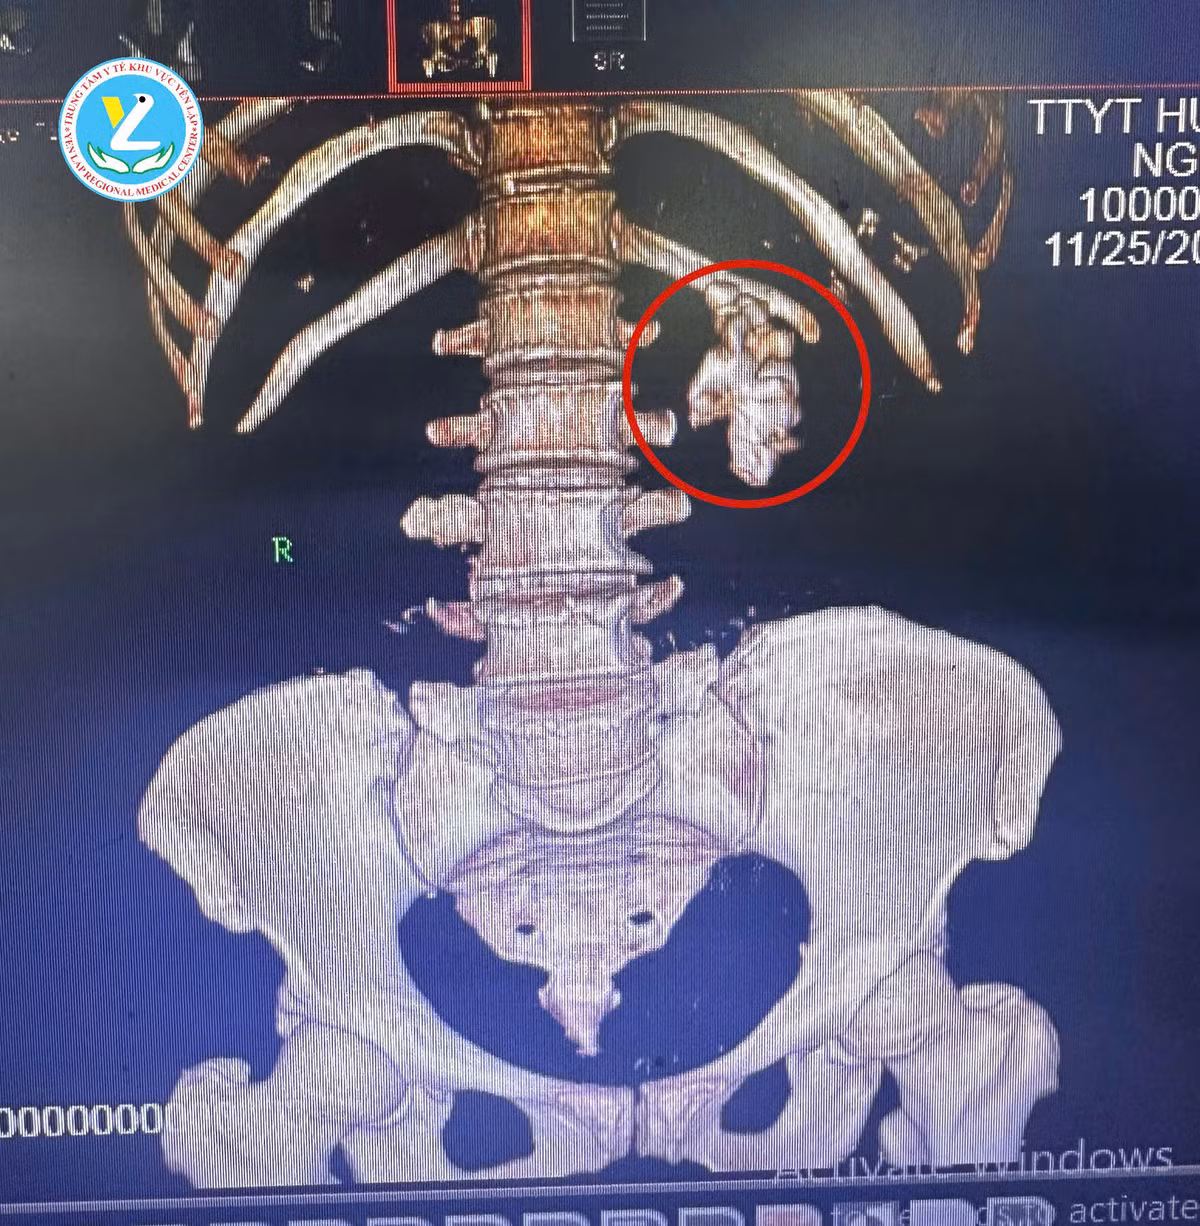

Sỏi san hô xâm lấn các đài bể thận - Ảnh BVCC

Nghi ngờ nguyên nhân sâu xa, người bệnh đến khám và điều trị tại khoa Ngoại tổng hợp – chuyên khoa, được các bác sĩ chẩn đoán “sỏi san hô thận trái”, có kích thước lớn 40x50mm, chiếm gần toàn bộ đài bể thận, gây ứ nước khiến nhiễm khuẩn tiết niệu không thể dứt điểm.